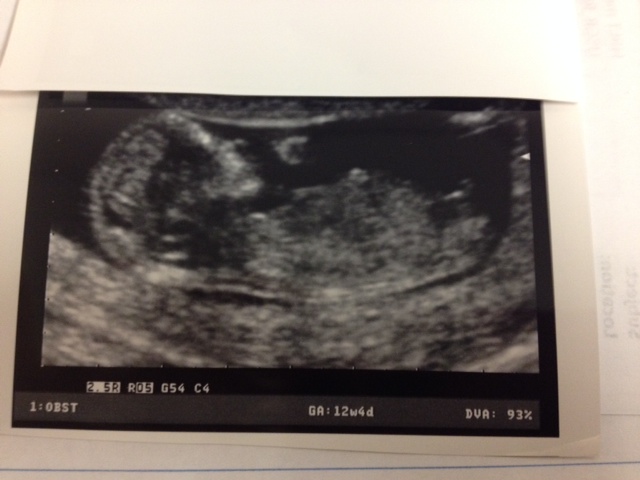

Hi ladies!! I had my 12w 4d u/s yesterday and I'm measuring 12w6d. I'm honestly not very good at the nub shot thing, so I'd love your guesses!!! I thought this would be the best picture to use, however I do have others if needed. Thanks so much!!!Attachment 15350